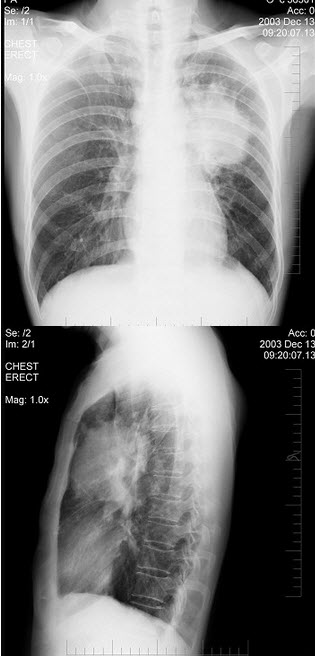

男,74岁,咳嗽,咳痰1月余,咯血丝痰1周伴胸痛,胸片如图所示,最可能的诊断为()

A.右上肺浸润型肺结核

B.右上肺不张

C.右侧中央型肺癌并右上肺不张

D.右侧包裹性积液

E.右肺上沟瘤